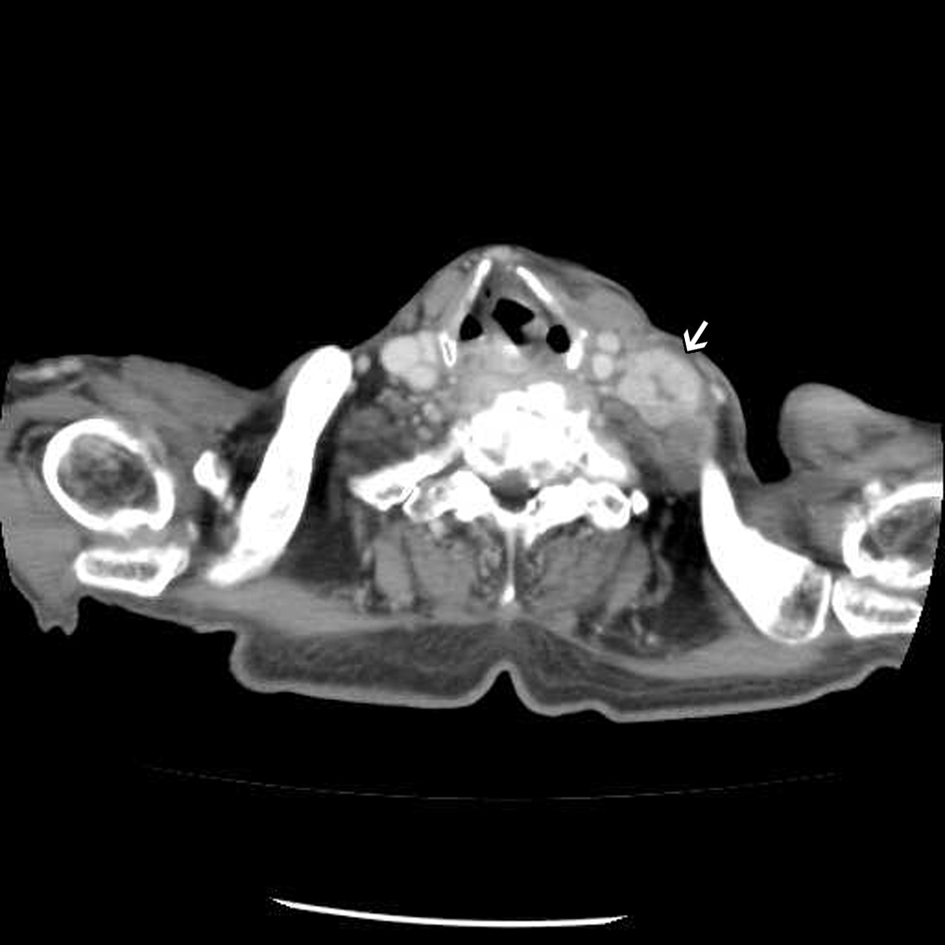

An 82-year-old male patient presented with chest tightness and shortness of breathing for 10 days. His past medical history included hypertension and old pulmonary tuberculosis. He suffered from productive cough for weeks and was referred to our center because of the worsening symptoms of dyspnea and lower leg edema noted over the past few days. On presentation, his consciousness was alert. Body temperature was 37.8 °C. Pulse was 136 per minute regular. Blood pressure was 164/90 mmHg. Oxygen saturation was 88%. Auscultation revealed decreased breathing sounds at left lung field and sonorous rhonchus at right lung field. X-ray of the chest showed left pneumothorax with collapse of left lung, and ground glass opacities in right lung field (Fig. 1), more in favor of inflammatory process at that time. He was admitted under the impression of right lung pneumonia with left pneumothorax and received chest tube insertion and empiric antibiotics treatment. However persistent air leak noted, he then received a chest CT for further survey. A chest CT showed nodular lesions over bilateral lung, with diffuse bone, left lower neck (Fig. 2), left suparclavicular, mediastinum, as well as right hilar (Fig. 3) and lower abdominal lymph nodes metastases. Unknown primary malignancy with bilateral lung metastases, diffuse bony metastases with left supraclavicular and left neck lymph node metastases was impressed and further tissue proof for possible underlying malignancy was recommended. For this reason, an echo guided biopsy with left neck lymph node biopsy was arranged for further study because the surgical intervention was not recommended for the patient due to poor lung function while patient declined bronchoscopy biopsy either. A subsequent neck lymph node biopsy revealed metastatic adenocarcinoma, while immunohistochemical stain for thyroid transcription factor -1(TTF-1), and cytokeratin 20 (CK20) are all negative. Serum tumor markers were examined in an attempt to identify the primary lesion, revealing a PSA level of > 1,000 ng/mL (normal < 4.0 ng/mL) while CEA 2.7 ng/mL (normal < 5.0 ng/mL). Digital rectal examination showed an enlarged and hardened left prostate lobe. An abdomen CT disclosed 4.3 × 3.0 cm ill defined heterogenous mass lesion at lower lobe of prostate (Fig. 4a) with regional and non-regional lymph nodes (Fig. 4b) and bony metastases. The urologist was consulted, and transrectal ultrasonography (TRUS) showed irregular urinary bladder wall thickening with enlargement of prostate, hypoechoic nodule with increased vascularity in left peripheral zone of prostate. Meanwhile the patient refused further tissue proof due to his poor general condition. The pathologist was informed of the elevated serum PSA and further clinical data, then an additional immunohistochemical staining of the left neck lymph node biopsy with P504S was performed as was compared to the regular H&E stain (Fig. 5a), the neoplastic cells expressed P504S diffusely (Fig. 5b), a metastatic adenocarcinoma of prostatic origin was confirmed. However his condition went downhill rapidly, and after thoroughly discussion with the patient and his family, they decided to receive hospice care and refused further intervention.

![]() Click for large image | Figure 2. Enhanced chest CT showing an enlarged lymph node at left lower neck. |